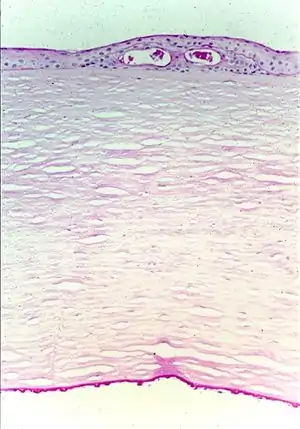

Fuchs corneal dystrophy. Light microscopic appearance of the cornea showing numerous excrescences (guttae) on the posterior surface of Descemet's membrane and the presence of cysts in the corneal epithelium beneath ectopically placed intraepithelial basement membrane. Periodic acid-Schiff stain. From a review by Klintworth, 2009.[1]

FECD is a degenerative disease of the corneal endothelium with accumulation of focal outgrowths called guttae (drops) and thickening of Descemet's membrane, leading to corneal edema and loss of vision. The corneal endothelial cell layer and its basement membrane (Descemet's membrane) acts as a barrier to hydration of the corneal stroma by aqueous humor and are "pump" cells of the cornea that function to maintain hydration of the cornea at a specific level that maintains corneal stromal clarity through precise spatial arrangement of collagen fibers. In FED, Descemet's membrane is grossly thickened with accumulation of abnormal wide-spaced collagen and numerous guttae. Corneal endothelial cells in end-stage FED are reduced in number and appear attenuated, causing progressive stromal edema (swelling). Progressive endothelial cell loss causes relative influx of aqueous humor into the cornea, leading to swelling (corneal stromal edema), which results in blurred vision. Eventually, the epithelium also becomes edematous, resulting in more severe visual impairment. Focal blisters of epithelial edema ("bullae") may be particularly painful when they burst.